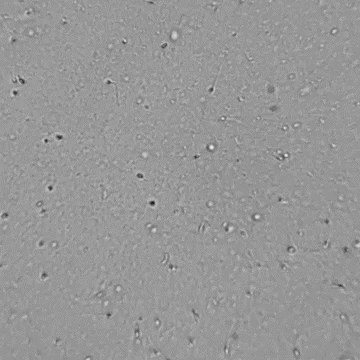

[NEW] 하고보고 정자 관찰기 2세트

집에서 간편하고 신속한 정자 상태 확인!